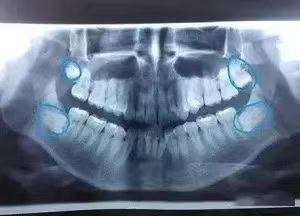

基於上述原因,當智齒的萌發對口腔健康構成威脅時,牙科醫生可能會建議進行拔除手術。拔牙前,醫生會進行全面評估,包括X光檢查,以確定智齒的位置和狀態,並根據具體情況決定最適合的治療方案。智齒拔除是一種常見的手術,技術成熟,風險相對較低,但術後仍需注意口腔衛生,遵循醫生的護理指導,以促進愈合並避免感染

- X光片是評估智齒狀態的重要工具。通過X光片,牙醫師可以了解智齒的實際位置、方向、鄰近牙齒與顎骨的關係,以及是否存在潛在的問題如牙根吸收、囊腫或腫瘤等。

根據阻生智齒的位置和方向,拔除的難度和風險也會有所不同。垂直阻生相對較易處理,而近中阻生或遠中阻生可能需要更複雜的手術程序。阻生智齒的確切類型往往需要通過X光片或CBCT(錐形束計算機斷層攝影)等影像學檢查來確定,以便醫生能正確評估情況並規劃適當的治療方案。